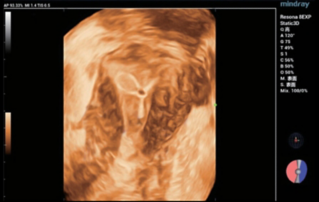

Endocavity ?? ?? ?? ???(DE10-3WU, Resona 7, Mindray)? ??? ??? ???? ?? ?? ????(Levator ani nuscle)? ??? ???. ???? ?? ??? 3~4mm? ????, ???(levator hiatus) ?? ?? - 6.13cm, LUG1(??? m ??? ??. Bulbocavernosus) ŌĆō 2.95cm ? LUG2 ŌĆō 3.15cm(?? 2.5cm ??)

??????? ??? ?? ? ??? ??? ??? ?????, ?? ??(pelvic floor) ??? ??? ?? ??(??? ?/?? ??)? ??? ???. ? ?? ???? PVA, RVA ? PUA ?? 20┬░ ???? ?????. ? ?? ???? PVA ŌĆō 134o, RVA ŌĆō 82o ? PUA ŌĆō 119o.

??? ???? ??? ?? ????? ??? ??? ?? ?????. ????? ? ??? 30mm?? 42mm?? ??? ? ??? ??? ??? ????? ?? ? ? ?? ? ?? ? ?? ??? ??? ??? ? ????. ?? R ? ???? ?? ?? ?? ?? ?? 7mm, ?? ?? 8mm???.